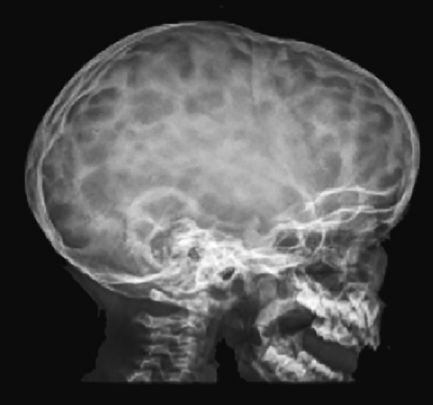

CHAPTER Normal skull growth and potential neurologic function may be affected by the presence of continued pressure in any one area of the cranium or by the presence of one or more pathologically fused cranial sutures. Posterior deformational plagiocephaly, most often secondary to a supine sleeping position, will generally resolve with positional changes, physiotherapy, or helmet therapy and is only rarely a surgical condition. The presence of a pathologically fused suture will produce deformity of the skull and is frequently an indication for operative release. The fused sutures determine the phenotype of the craniofacial deformity. According to Virchow’s Law, bone growth can no longer occur across (perpendicular to) the affected suture and therefore only occurs along it (parallel)1 (Fig. 41.1). Craniosynostosis can be classified into simple (single suture) versus complex (multiple sutures) and nonsyndromic versus syndromic subtypes. Assessment of an infant with an abnormal head shape includes a detailed medical history and physical examination to rule out a positional cause and identify any complicating sequelae. The medical history should identify any history of skull irregularities, associated syndromes, family history of calvarial deformities, and symptoms of intracranial hypertension (headache or vomiting, developmental changes, irritability, or oculomotor paresis). Often, parents note an abnormal head shape at the time of delivery or one that becomes more apparent later in infancy. Patients with irritability, feeding difficulties, failure to thrive, headache, developmental delays, visual changes, marked turricephaly, supraorbital recession, bulging or “tight” fontanels, abnormal distended scalp veins, or a lack of circumferential skull growth may have an increase in intracranial pressure. For patients with head shape abnormalities, a careful physical examination should be able to identify the cause. Positional deformation presents with a classic parallelogram appearance when looking from above. Skull deformation caused by premature fusion produces characteristic findings, including asymmetry (supraorbital retrusion, towering or turricephaly, frontal or occipital bossing), inability to palpate the anterior fontanelle (which normally remains open until 12 to 18 months of age), perisutural ridging, and signs of intracranial hypertension (papilledema). Studies have shown that the presence of intracranial hypertension is dependent on the number of affected sutures, ranging from approximately 14% for single-suture synostosis to approximately 47% in multisuture synostosis.2,3 Suture release in craniosynostosis is often offered to correct the craniofacial deformity and to address potential increased intracranial pressure that in some patients has resulted in blindness and developmental delay. Fig. 41.1 Virchow’s law: Bone growth can no longer occur across (perpendicular to) a fused suture and therefore only occurs along it (parallel). The specific calvarial shape can indicate which sutures are involved. Children with sagittal synostosis present with a narrow, elongated skull (dolichocephaly describes long-headedness; scaphocephaly describes a boat-shaped head). Depending on the region of greatest fusion of the sagittal suture, the child may manifest frontal or occipital bossing or a combination of both. Some children will also demonstrate a “towering” skull, also known as turricephaly. Metopic synostosis is marked by a variable degree of phenotypic severity, ranging from mild ridging to the formation of a triangular head (trigonocephaly) or prominent “keel” forehead with or without hypotelorism. Although an endocranial ridge is not commonly seen in patients with metopic synostosis, an endocranial notch can be observed on axial CT images and is virtually diagnostic of pathologic suture fusion. Patients with unicoronal synostosis present with anterior plagiocephaly, whereas those with bilateral coronal involvement demonstrate brachycephaly. Phenotypic features of anterior plagiocephaly include ipsilateral perisutural ridging, forehead flattening, and orbital recession, coupled with contralateral compensatory frontal bossing. Facial deformities are also common, including nasal root displacement toward the ipsilateral side, anterior displacement of the ipsilateral ear, and chin deviation toward the contralateral side, resulting in a classic C-shaped craniofacial deformity—concave contralateral to the fused suture. Children with lambdoid synostosis characteristically have a trapezoid-shaped head (seen from the vertex view) in association with posterior displacement of the ipsilateral ear, contralateral occipital bossing, ipsilateral mastoid bossing, and ridging of the affected lambdoid suture. In contrast, posterior deformational plagiocephaly is marked by a parallelogram-shaped head when viewed from the vertex, anterior displacement of the ipsilateral ear, ipsilateral frontal bossing in the absence of palpable lambdoid suture ridge, and no mastoid bossing as is seen with lambdoid suture fusion (Fig. 41.2). Posterior plagiocephaly caused by lambdoid suture synostosis is rare; the majority of posterior plagiocephaly is secondary to positional molding. Understanding the phenotypic differences between lambdoid synostosis and posterior deformational plagiocephaly is critical for making the appropriate diagnosis and designing the proper course of treatment. Head circumferences, cranial indices, and anthropometric measurements should also be noted. Imaging studies may be necessary to confirm the diagnosis and rule out any associated intracranial abnormalities. For younger patients, ultrasonography has been used as a screening tool to visualize the sutures through the open fontanelles. Although not as sensitive as computed tomography (CT), it avoids the risk of radiation exposure. CT remains the most sensitive modality to assess bony sutural fusion and may suggest elevated intracranial pressure, as noted by areas of erosion of the inner calvarial table (“copper-beaten” appearance) (Fig. 41.3). Pathognomonic for unicoronal synostosis, elevation of the ipsilateral orbit can be seen secondary to superior displacement of the greater wing of the sphenoid, also known as the “harlequin” deformity. Modern CT protocols attempt to minimize the radiation dose to the infant.4 Both CT and magnetic resonance imaging (MRI) are helpful in evaluating the underlying brain for structural or functional abnormalities, including hydrocephalus, holoprosencephaly, cortical dysplasias, and Chiari malformations. The latter are structural defects in the part of the brain that controls balance (cerebellum). Without sufficient space, the cerebellum and parts of the brain stem may sit too low, causing pressure and blocking the flow of cerebrospinal fluid. This is important to identify preoperatively, because intraoperative maneuvers may worsen the condition. Summary Box Common Complications in Synostosis Correction Intraoperative • Bleeding • Venous air embolism • Ocular injury and vision loss • Dural and brain injury, cerebrospinal fluid leak • Death Postoperative • Infection • Growing skull defects • Persistent calvarial defect • Hardware-related complication • Restenosis, relapse, growth restriction, and recurrence of deformity Surgical intervention is indicated in craniosynostosis to correct the craniofacial deformity and potentially treat or prevent functional disabilities believed to be secondary to intracranial hypertension (blindness, developmental de lay, psychosocial dysfunction). Patients with multisutural synostoses present with increased severity of physical and neurologic symptoms; therefore surgical intervention is even more important. The optimal surgical age has been debated, because the techniques of surgery are variable. Although the literature is inconclusive regarding the appropriate timing for correction of craniosynostosis, most craniofacial surgeons operate within the first year of age, taking into consideration the number and pattern of suture fusion, evidence of intracranial hypertension, and the surgical technique chosen. Minimally invasive techniques, which rely on less extensive craniotomies and external postoperative molding, are generally performed at an earlier age than are traditional open techniques. The technical portions of the procedures are complicated and have multiple risks. Avoidance of these risks is important to produce improved results. This begins with carefully evaluating potential patients preoperatively and optimizing their physical condition before surgery. In preparation for surgery, measures to ensure stable blood volumes should be undertaken. These include obtaining a baseline hemoglobin, blood type and crossmatch, and potential directed blood donation from a matched family member. Some surgeons use preoperative erythropoietin to minimize the need for transfusion.5 Surgery is performed under general anesthesia, which should be provided by a fellowship-trained pediatric anesthesiologist. Patients should be monitored postoperatively in an intensive care unit under the direction of pediatric critical care–trained physicians. A broad range of surgical options has been proposed for the surgical treatment of craniosynostosis. The goal of each is to remove the affected suture and either immediately remodel the remaining calvarial vault or provide postoperative guidance (distractors, springs, helmets) to allow this to occur. For most types of craniosynostosis repairs, patients are placed in the supine position to facilitate exposure. However, if the posterior vault is being addressed, as in a lambdoidal synostosis or some sagittal synostoses, the patient may be placed in the prone or sphinx position . In the prone position, care must be taken to ensure proper positioning with adequate protection of the eyes. Injury to the globe is devastating and should be a “never event.” Before the procedure begins, lubrication should be placed over the corneas; some surgeons approximate the eyelids with either adhesive tapes or formal tarsorrhaphy sutures that can be removed at the conclusion of the procedure. If the patient must be in the prone position, the face can be supported with a foam pillow or horseshoe headrest, with the eyes uncompressed within the opening of the support. Venous air embolism (VAE) is the introduction of air or gas from the operative field into either the arterial or venous vasculature and is a potentially fatal complication of neurosurgical procedures.6 Previous studies have suggested that the rate of VAE may be as high as 80% during such procedures. This may be lower for endoscopic techniques.7 Some believe that real-time monitoring, to identify the presence of a venous air embolism and allow for immediate intervention, mitigates the risk. Despite the introduction of newer diagnostic techniques, use of a precordial Doppler remains a standard modality. Although transesophageal echocardiography is the most sensitive method of detection,8,9 it is more costly and invasive. When properly placed between the third and sixth intercostal spaces along the right parasternal border, a precordial Doppler is potentially capable of identifying VAE at an air infusion rate as low as 0.015 mL/kg/min and consistently at a rate of 0.021 mL/kg/min.10,11 VAE may be graded by severity: change in Doppler tones (grade I), change in Doppler tones and decrease in end-tidal carbon dioxide (grade II), or decrease in systolic blood pressure by 20% from baseline (grade III). The calvarium is often approached via a standard “stealth” (zigzag) coronal incision, providing for adequate exposure while minimizing any postoperative scar. Perioperative antibiotics and steroids may be administered before the procedure. The incision is infiltrated with 1:200,000 epinephrine in 0.5% lidocaine to minimize bleeding along the incision site. The frontal and temporal regions are dissected in the subgaleal plane, and care is taken to preserve the periosteum on the surface of the bone, which helps minimize blood loss and may be used to stabilize the bony segments. Bleeding can occur at several points in the procedure. Incisions into the scalp can produce significant bleeding in the infant. This bleeding can be controlled with metal clips and cautery. Bleeding can also occur with elevation of the coronal flap. This is usually greater with subperiosteal dissection rather than supraperiosteal dissection. With either, punctate bleeding should be controlled with pinpoint cautery or bone wax. The latter should be used judiciously, because any wax left behind can serve as a nidus for infection. To “turn down” or reflect the coronal flap, the supraorbital vessels must be released from their attachments to the frontal bone. Sometimes, the vessels exit the bone through a notch; in older children they exit through a foramen. If the surgeon is not careful of these vessels, unnecessary bleeding can occur. When the vessels may exit through a foramen, a 2-mm osteotome should be used to convert the foramen to a notch by removing the inferior portion with the bony foramen. The vessels within the underlying periorbita can then be carefully dissected away from the bone. Performing the craniectomy involves making several small access holes and joining them with a side-cutting craniotome with a protective footplate. The access holes are made with a high-speed burr. Injury may occur if the burr is used too aggressively to enter the calvarial vault. The burr is often used to traverse the outer table, diploic space, and a portion of the inner table. As the remaining bone becomes thin enough, the burr can be put aside and communication to the epidural space made with a fine curette. Once a small opening is made with the curette, a Kerrison rongeur can be used to widen the opening further. The Kerrison has a protective footplate to minimize dural injury. Once the opening is large enough, a small elevator, such as a No. 4 Penfield, can be used to dissect beneath the bone and above the dura along the proposed craniotomy path. Once the bone cuts have been made, the bone flap should be removed carefully to avoid additional trauma to the underlying dura from sharp edges. The most severe bleeding can occur if there is injury to the sagittal sinus. The sagittal sinus is most at risk when the craniotome passes across the midline. For this reason, any cuts traversing the sagittal sinus are performed last. In the event of significant bleeding, the bone flap can then be removed relatively quickly to address the blood loss. With the remaining bone cuts already performed, the bone flap can be removed relatively quickly and any bleeding controlled. Injury to the sagittal sinus more posterior in the skull is more worrisome. The earliest approaches to treating craniosynostosis included simple suturectomy, allowing the brain to direct skull growth through the remaining open sutures. Inadequate correction prompted more extensive procedures of calvarial remodeling, and these have yielded improved results. These current techniques include wide scalp dissection, more remote calvarial osteotomies, and skull remodeling that is individually tailored to each cranial vault deformity.12 For sagittal synostosis, the surgical approaches range from minimal removal of the involved suture (usually combined with postoperative use of springs, distractors, or helmets) to extensive total calvarectomy and reconfiguration. Simple synostectomy, or simple strip craniectomy, when combined with postoperative springs, distractors, or helmet therapy, can be safe and well tolerated, providing adequate cosmetic results in select patients with mild deformities. Disadvantages include its lack of specifically addressing the severe compensatory changes in skull shape that result from the fused suture. It also leaves a large unprotected area over the vertex of the skull, an area with a high rate of restenosis and renewed growth restriction. The midvault “expanded strip craniectomy” provides a more immediate reconstruction of skull contour by shortening the anteroposterior dimension, expanding the biparietal dimension, and partially addressing the frontal and occipital prominences. The “Pi reconstruction,” a version of a midvault expanded strip craniectomy, is used for older infants (6 to 12 months of age) with scaphocephaly caused by sagittal synostosis (Fig. 41.4). Bone is removed lateral to the sagittal suture over the lateral parietal areas and molded, leaving two bony defects in the design of the Greek letter Pi (π). Cranial bone overlying the sagittal sinus is left intact to minimize bleeding. Axial compression is used to shorten and widen the skull, and absorbable plates are placed to hold the position. For coronal and metopic synostosis, the goal is to correct the frontal and orbital asymmetries. In the former, there is asymmetry in the shape of the orbits and forehead. In the latter, the typical deformity involves a midline ridge with retrusion of the supraorbital bar (“bandeau”) on either side of the forehead. The most common technique is fronto-orbital advancement (FOA). With an FOA, dissection continues within the orbits, freeing the periorbita off the upper half of the orbit. Caution must be taken to avoid injury to the underlying globes. To expose the roof of the orbits or anterior cranial base, a bifrontal craniotomy is marked and cut with an osteotome. Typically 1 to 2 centimeters of the superior orbital rim is left for support. The bone flap is placed aside and replaced in a more corrected position at the end of the procedure The supraorbital bar or bandeau is removed with careful osteotomies through the lateral orbit at the frontozygomatic suture, the superior orbit along the roof, and the nasion just above the nasofrontal suture. Care is taken to protect the underlying dura and brain as well as the orbital contents with adequate exposure and judicious use of retractors. This is a relatively low-risk maneuver but should similarly be performed with caution. The eyes are perhaps most at risk when cutting the orbital bandeau. Here, sufficiently wide malleable retractors should be placed between the globes and the saw blade or osteotome. The saw should not be run unless there is good protection of the underlying structures and the blade only advanced through the bone as far as needed. As the blade moves either medially or laterally, the retractors should follow to avoid inadvertent injury. The sphenoid wing is cut and the coronal sutures are opened to the level of the skull base to prevent continued growth restriction and resultant postoperative hollowing of the pterional regions. The bandeau is then reconfigured and fixed with resorbable sutures or plates and screws to maintain the newly contoured shape. Reconfiguration of the supraorbital bar might require osteotomies, both in the midline to flatten the forehead and laterally to normalize the lateral supraorbital angle. The goal is expansion on the affected side as well as recession on the contralateral side. When replaced, its lateral aspects and midline are fixed to the calvarial vault. This is performed for both unilateral and bilateral cases. To avoid relapse or a persistent deformity, overcorrecting the expansion of the affected side by 5 to 10% while also providing a convex shape at the lateral border is commonly necessary for a satisfactory reconstruction. The frontal bone flap is then attached to the supraorbital bar, taking care to match it to the previously overcorrected (5 to 10%) orbital bandeau on the affected side. For lambdoid synostosis, a variety of surgical approaches, aiming to release the affected suture(s) and normalize the posterior calvarial vault contour, have been described. Options include simple synostectomy, unilateral remodeling of the affected occipital region, and bilateral occipital reconstruction with or without the use of an occipital bandeau. Most lambdoid surgical candidates have significant parietal and frontal compensatory changes in addition to their occipital deformation; therefore they are best served by a more extended calvarectomy and remodeling. The reconstruction is similarly maintained with intervening bone grafts and resorbable hardware. Titanium was used early on but fell out of favor when it was noted that the plates translocated endocranially to the internal surface of the skull with calvarial growth. Resorbable plates made of polylactic acid provide temporary support across the osteotomy sites and dissolve within 12 to 24 months. After placement of the reconfigured supraorbital bar, the frontal bone is remodeled using the remaining portions of bone and fixed with absorbable plates or suture. Closure is performed in a routine fashion, with some surgeons placing subgaleal drains. To address concerns regarding incision length, operative blood loss, and length of stay associated with open cranio-facial procedures, minimally invasive techniques have been proposed. These techniques include endoscopic sutural release,13 spring-assisted cranioplasty14 (Fig. 41.5), and distraction osteogenesis15 (Fig. 41.6). Endoscopic release has been proposed to minimize the intraoperative risks by limiting the amount of bleeding from larger scalp incisions and bone flap elevation. The technique uses one or more small incisions, minimal dissection, and removal of the affected suture, possibly with adjunctive osteotomies into the surrounding bone. The technique does not attempt to completely correct the craniofacial deformity at the time of surgery but rather remove the offending sutures and allow remodeling during a period of postoperative brain growth, with or without external molding, or distractive force. The use of springs works in a similar fashion; the affected suture is removed and one or more internal springs are placed across the open osteotomy to guide remodeling of the skull (see Fig. 41.5). Of note, a second, smaller procedure is required to remove the springs. Similarly, distraction osteogenesis has been used to impart an internal force across the ostectomy site (see Fig. 41.6). New bone is laid down in the distracted osteotomy gap.